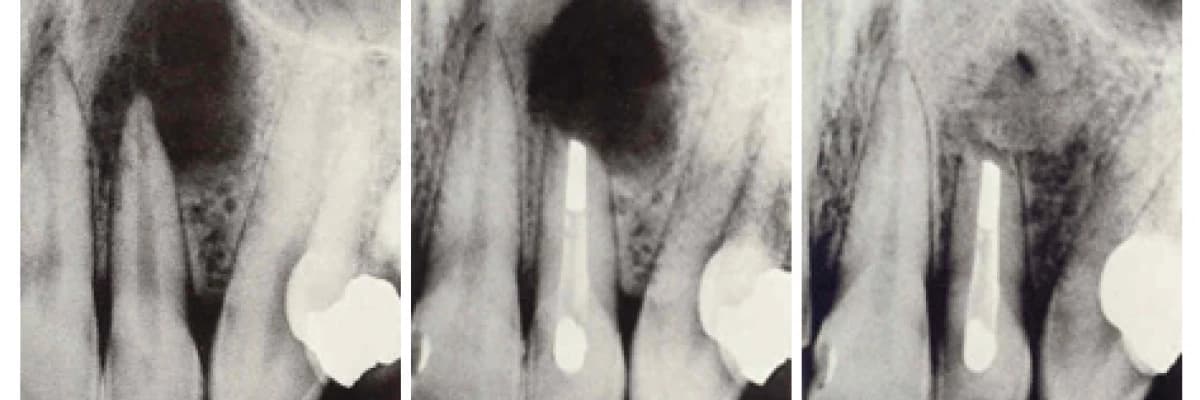

APİKAL REZEKSİYON

Diş kökünde çeşitli nedenlerle meydana gelen apse veya kistik lezyonlar, kanal tedavisi uygulamasının yetersiz kaldığı durumlarda direkt olarak açılıp enfekte kök bölgesinin kesilip çıkartılmasıyla tedavi edilmeye çalışılır. Bu uygulamaya apikal rezeksiyon işlemi denir. Apikal rezeksiyon dişin çekiminden önce değerlendirilmesi gereken bir tedavi seçeneğidir.